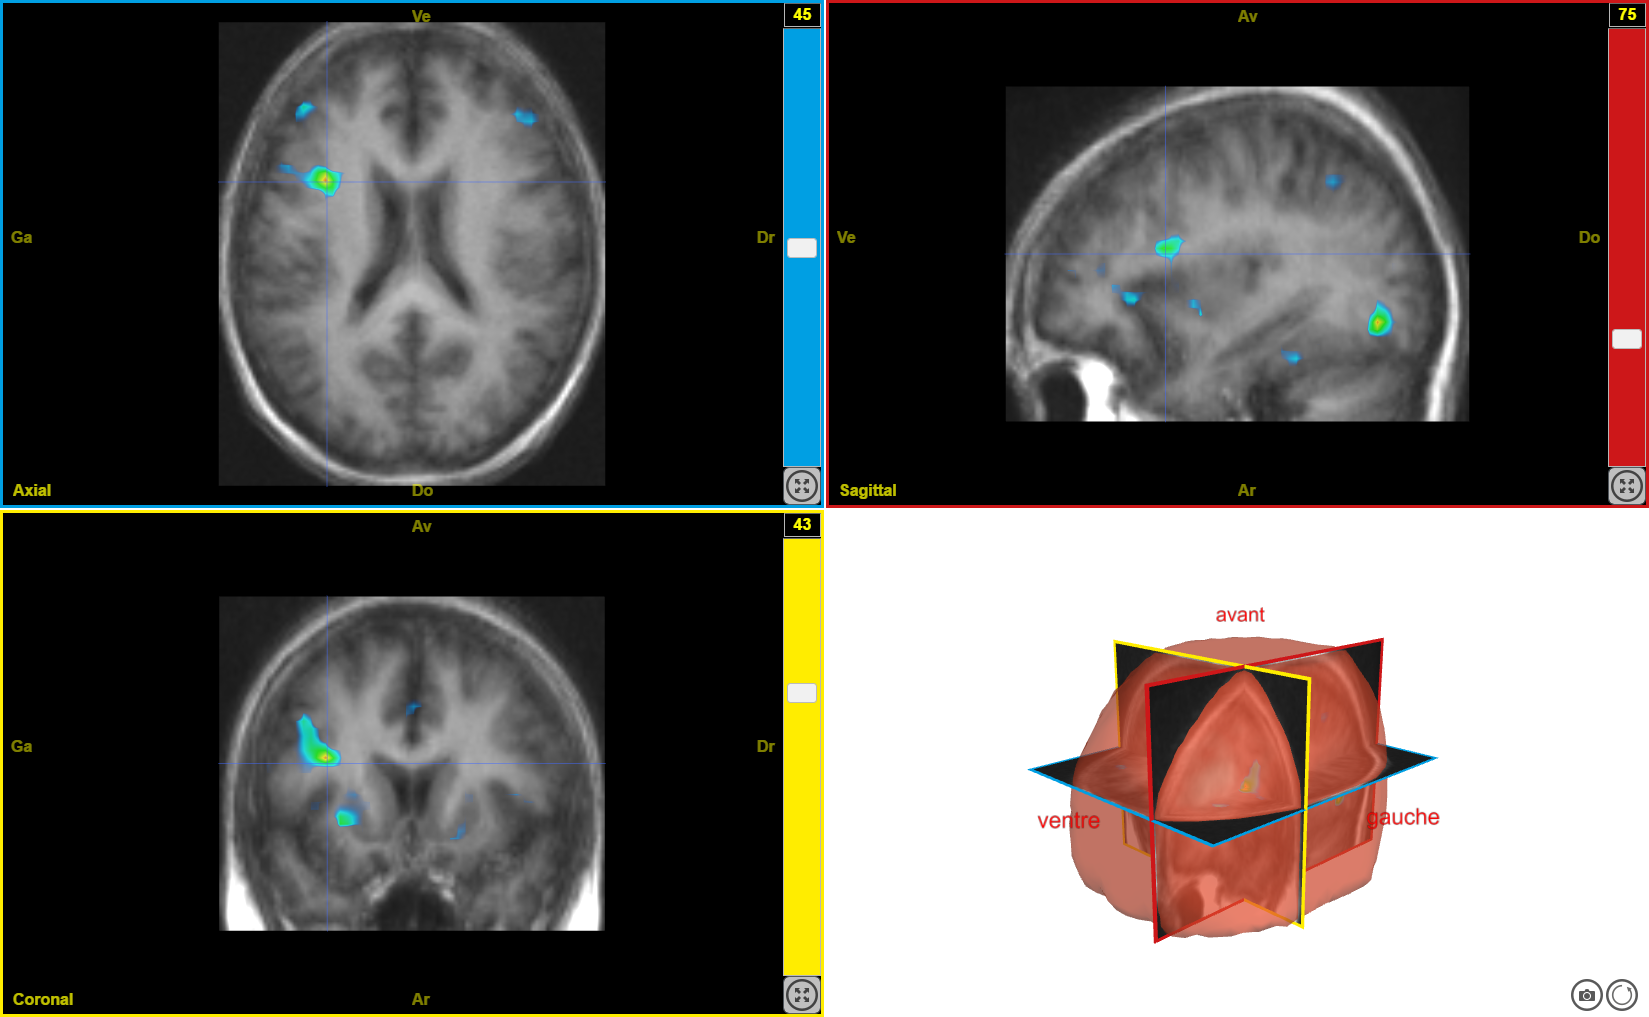

scenar9

Ancien logiciel : EduAnatomist et Neuropeda

Informations sur les images AnaPeda

Exemple de lien direct vers EduAnat 2 en ligne